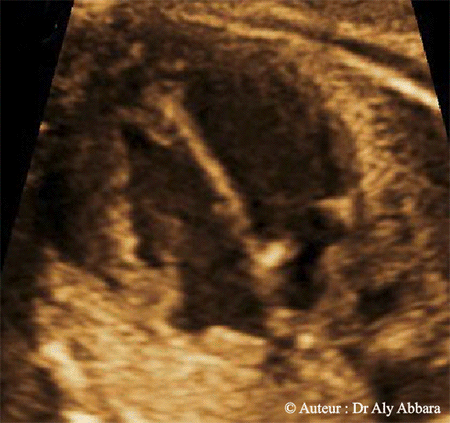

Cœur fœtal : la coupe des quatre cavités cardiaques :

Sur cette coupe ; les éléments anatomiques suivants peuvent être mis en évidence :

• Le ventricule gauche (VG) et le ventricule droit (VD), puis le septum inter-ventriculaire séparant parfaitement ces deux ventricules.

• L'oreillette gauche (OG) et l'oreillette droite (OD), puis le septum inter-auriculaire séparant partiellement ces deux oreillettes ; en effet, l'oreillette droite communique avec l'oreillette gauche par l'intermédiaire du foramen ovale (une fenêtre située dans le septum inter-auriculaire).

• Les deux valves auriculo-ventriculaires droite et gauche, c'est-à-dire, respectivement : la valve tricuspide et la valve mitrale.

L'insertion de la valve mitrale sur le septum inter-ventriculaire est décalée légèrement vers le haut par rapport à l'insertion de la valve tricuspide sur le même septum (donc cette valve est légèrement plus bas par rapport à la valve mitrale).

• Une coupe transversale sur l'aorte descendante ; cette coupe est identifiable derrière l'oreillette gauche et légèrement à gauche de la face antérieure du corps vertébral.